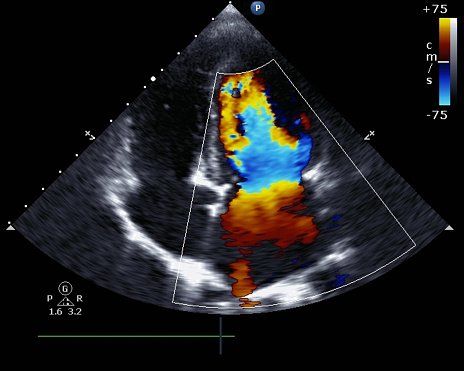

Ecocolordoppler

Ecocolordoppler venoso e arterioso degli arti inferiori e/o superiori, dei tronchi sovraortici, dell'aorta addominale e delle arterie renali.